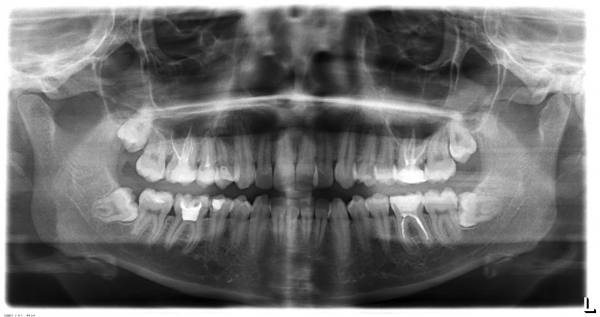

Образовался флюс, открыли канал, рассекли десну, выпустили гной, поставили дренаж, назначили полоскание содой. Прошло пять дней. Прихожу к доктору, ковырнула иголкой в зубе, не болит. Сказала, у вас киста, надо делать операцию. Не поверил, сходил в другую клинику, сделали снимок, посмотрели, говорит доктор, нету там никакой кисты. Пошел в третью клинику, показал снимок, показал зуб - прочистили, промыли, кисты не нашли.

Кисты, конечно, тут нет, но обширное воспаление и, как следствие, обострение периодонтита, наблюдается. Данную проблему можно разрешить консервативным методом лечения, то есть через канал. Обратитесь к грамотному терапевту.